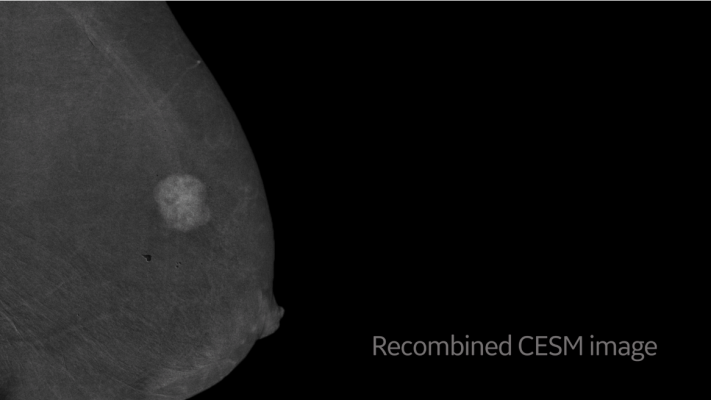

Key to this revolutionary change in breast care is GE Healthcare’s SenoBright HD Contrast Enhanced Spectral Mammography (CESM), a diagnostic imaging tool that can detect malignant lesions not seen on mammography or ultrasound in certain cases. By highlighting areas of unusual blood flow to help localize lesions that need to be biopsied, CESM biopsy — Serena Bright — helps improve radiologists’ diagnostic confidence with the ultimate goal of getting answers to patients as quickly as possible.